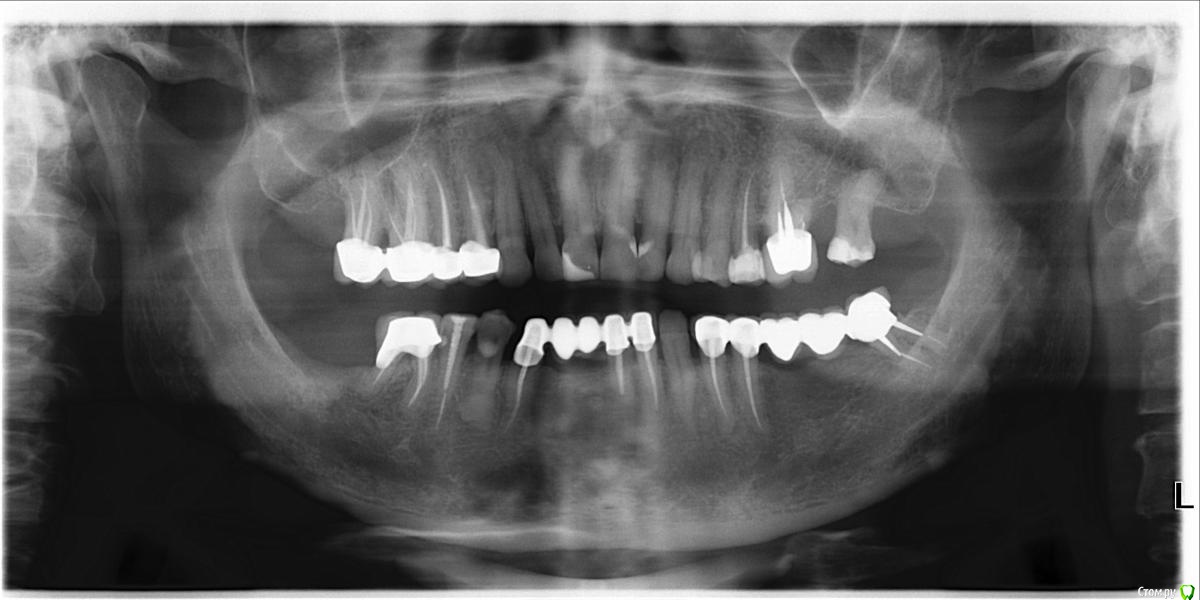

СеменМ Опубликовано 14 октября, 2019 Поделиться Опубликовано 14 октября, 2019 Время от времени, при плохой погоде болят зубы. один перестает начинает другой и так по кругу. Невралгия тройничного нерва? Оголены корни? Инфекция? Ссылка на комментарий

Saymon Опубликовано 18 октября, 2019 Поделиться Опубликовано 18 октября, 2019 (изменено) Добрый день. В Вашем случае, лучше обратиться на очный осмотр к доктору терапевту и пародонтологу. Нужно смотреть, трогать и так далее. Изменено 18 октября, 2019 пользователем Saymon Ссылка на комментарий